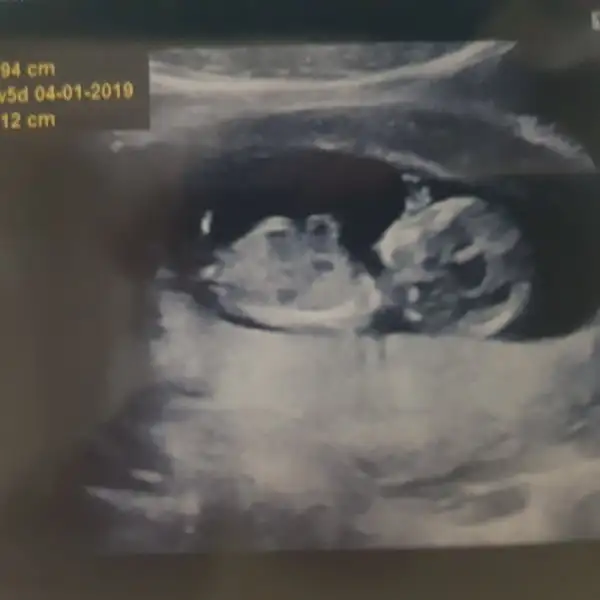

Canım erkek gibi duruyor

kiza benzettim canimHerkeze iyi akşamlar benim melegimede dr kıza benziyo ama 1 ay sonra erkek diyebilirim dedi sizce ????

Yorumun için teşekkürler canımCanım erkek gibi duruyor![]()

dr etkilendim sanirim kizim demeye başladımkiza benzettim canim